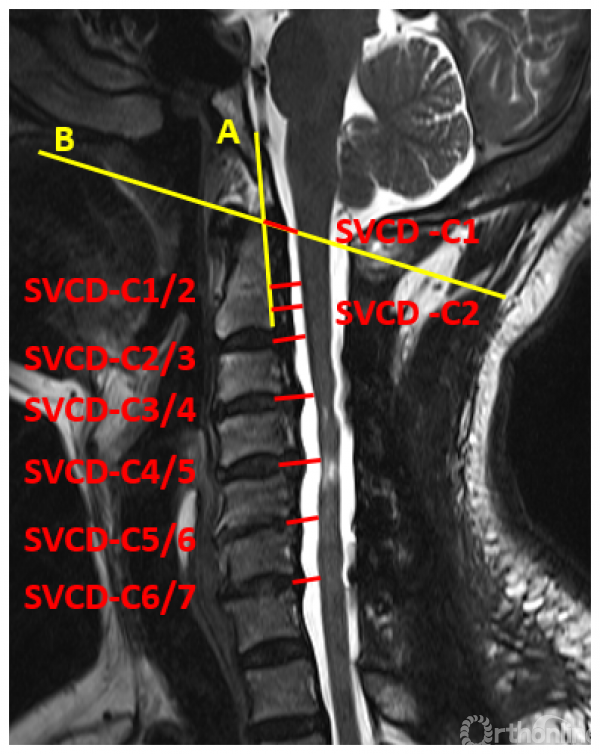

于是,我们回顾性分析了45例含上颈椎后路减压的压迫性颈脊髓病患者的临床资料,按减压范围分为C2-7组(25例)和C1-7组(20例)。利用本系列研究第三部分建立的方法,对两组各个节段的椎髓间距(VCD)进行测量和比较。与之前的研究不同的是,为了避免由于上颈椎形态不规则对测量造成的影响,将参数测量方法人为的标准化,称为标准化椎髓间距(standardized vertebral -cord distance, SVCD),并对测量位点进行了细化,增加了寰椎水平的数据(记为SVCD-C1)、枢椎齿突与枢椎椎体结合部的数据(记为SVCD-C1/2)、枢椎椎体中部水平的数据(记为SVCD-C2)(图1)。并对各个节段的SVCD进行组间比较。

图1

结果显示不仅在C1水平,C1-2及C2水平的SVCD在两组间也有显著差异(图2)。而在C2/3及以下节段,两组间均无显著差异。也就是说,在C2-7减压的基础上切除寰椎后弓,因此而减压效果获益的区域仅限于C1至C2椎体中部区域(图3),无助于C2/3及以下节段减压效果的提高。

图2

图3

通过正态性检验,我们还可以进一步估算两组在C1/2及C2水平致压物大小与压迫残留几率的关系,选择合理的临界值。在C1/2水平致压物矢状径为8.5mm时,C2-7减压在该水平压迫残留率为54.70%,C1-7减压在该水平压迫残留率降低至16.26%;C2水平致压物矢状径为8.5mm时,C2-7与C1-7减压在该水平压迫残留率分别为57.76%与28.82%。

寰椎后弓切除显著提高了颈后路手术在上述测量水平的减压效果。8.5mm可作为在C1/2和C2水平致压物矢状径的临界值。当致压物在C1/2或C2水平超过8.5mm时,即使在寰椎水平无脊髓受压,仍建议向头侧扩大减压切除寰椎后弓,以获得更好的减压效果。

当OPLL累及上颈椎时,需要权衡是否需要切除C1后弓的情况并不少见,本研究有助于合理确定寰椎后弓切除的指征。除了寰椎水平脊髓腹侧(如颈椎后纵韧带骨化延伸至寰椎前弓)或背侧(寰椎后弓发育不良或畸形)存在压迫这一常见手术指征,在寰椎至枢椎体中部范围内,当致压物的矢状径超过采用C2-7减压能获得的SVCD(8.5mm)时,向头端扩大减压,行寰椎后弓切除是获得充分减压的有效手段(图4)。